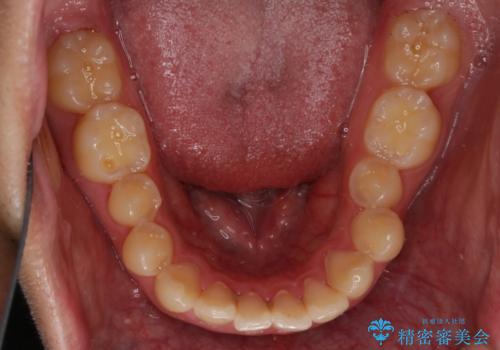

- 上の前歯が見えすぎて気になるとご相談にいらした方です。インビザラインにて前歯の圧下を行うことで歯の見え方の改善し、同時に奥歯の噛み合わせも改善を行いました。

インビザラインを正しく使用して頂けたおかげで、比較的難しいとされる歯の圧下も補助装置を使用せずに行うことが出来ました。上の前歯のラインが整ったことで笑った時の口元の印象を改善させることができ、大変喜んでいただけました。